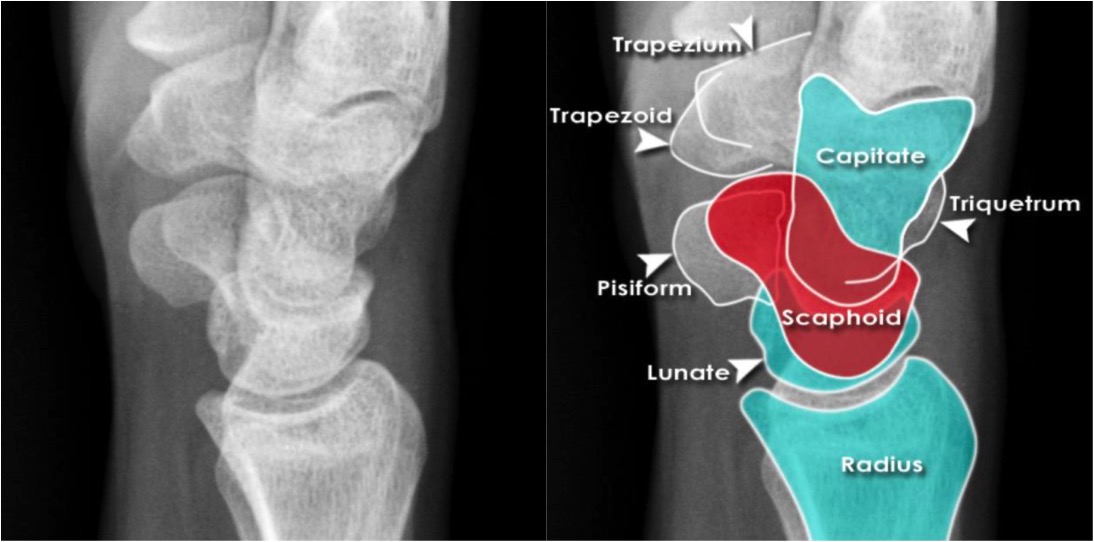

Wrist Trauma Radiographic Evaluation - Hand - Orthobullets